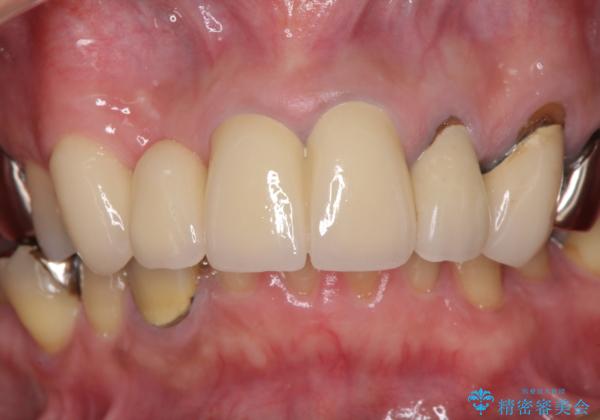

欠けてしまった前歯のブリッジをオールセラミックブリッジへ

歯肉が少し退縮していたため、補綴治療のやり直しにより歯が少し長く見えるようになりましたが、自然な口元に仕上がり、患者様には大変満足していただきました。

定期的にラグビーをされるとのことなので、マウスピースの装着をかかさないようにお伝えしました。